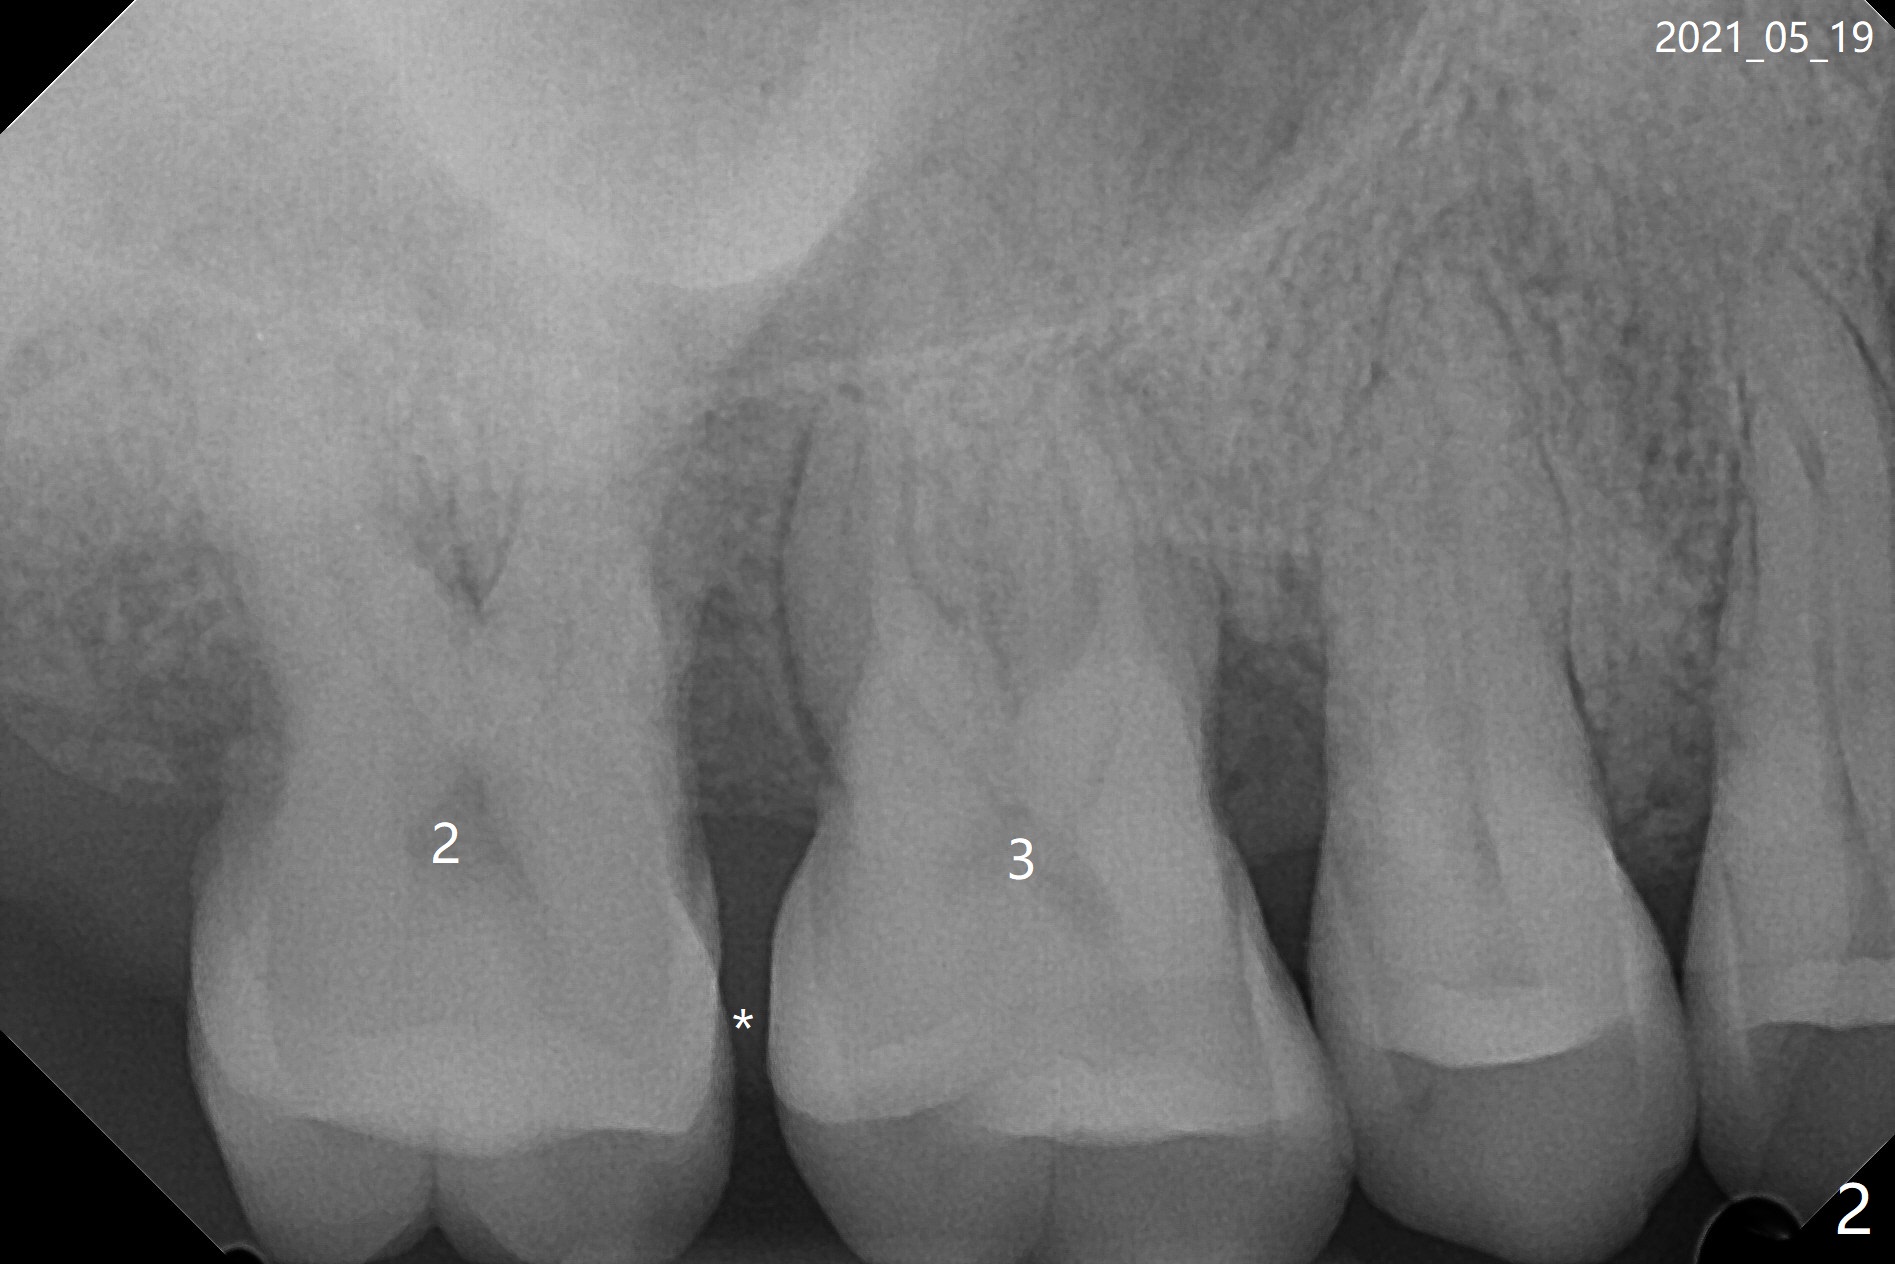

47岁女31号牙即刻种植术后一个月,2,3之间牙周炎发作(图一,二),局麻下,再次局部深些(四个月后),放置Arestin。